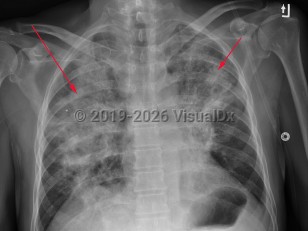

COVID-19